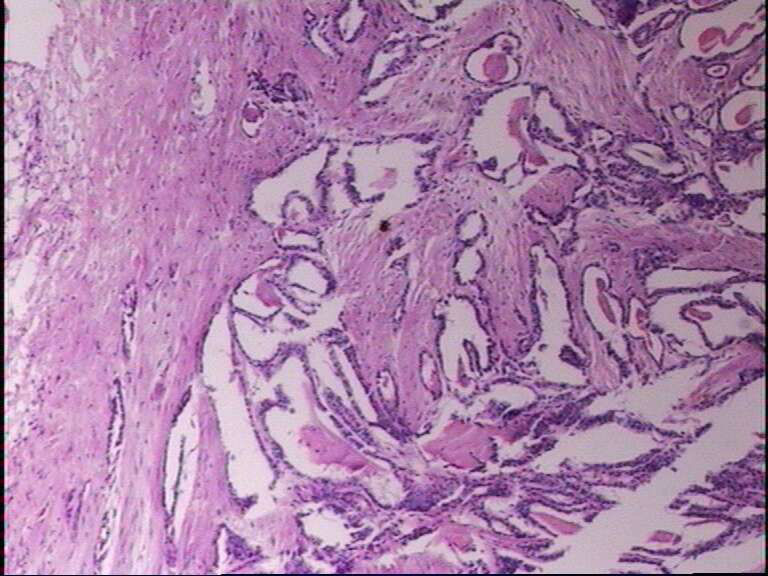

女43岁,甲状腺肿物